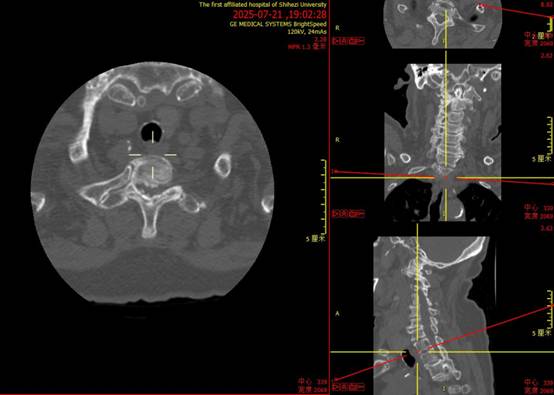

▲图为术前椎管内受压情况